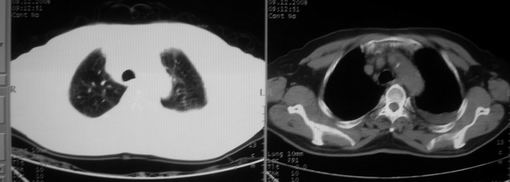

男,78岁,咳嗽、咳痰、发热入院,抗炎治疗一周后已退热,咳血似痰。

10月3日片: